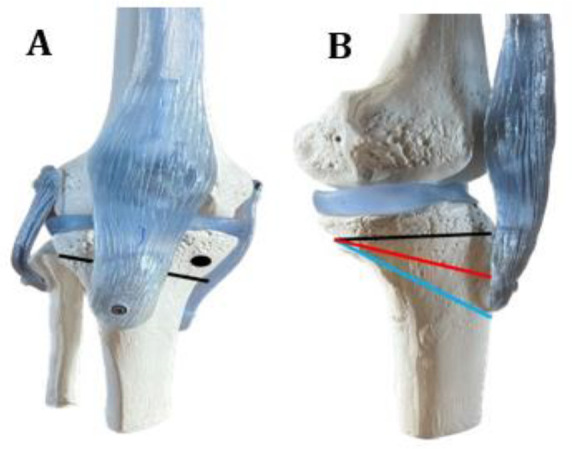

同时进行前交叉韧带(ACL)重建(ACLR)和外翻高胫骨截骨术(HTO)可减轻70%前交叉韧带缺损和股胫骨骨关节炎患者的疼痛,使膝关节在10年随访中保持稳定,33%-80%的病例可重返运动场(RTS),但39%的病例会出现股胫骨骨关节炎进展。并发症发生率为 0% 至 23.5%(6.5% 为翻修外翻 HTO,17.5% 为前交叉韧带移植失败,7.7% 为静脉血栓)。对于患有前交叉韧带缺损和股胫骨屈曲性骨关节炎并伴有胫骨后斜坡过高(PTS)的患者,同时进行前交叉韧带重建和HTO可获得令人满意的效果,而且似乎对重建后的前交叉韧带进一步断裂具有保护作用。患者年龄越小、运动需求越多,我们就越倾向于进行联合干预(前交叉韧带重建和外翻 HTO)。

Simultaneous anterior cruciate ligament (ACL) reconstruction (ACLR) and valgus high tibial osteotomy (HTO) alleviates pain in 70% of individuals with ACL deficiency and varus femorotibial osteoarthritis, allows for sustainable stabilization of the knee at the 10-year follow-up and a return to sport (RTS) in 33%-80% of cases, but femorotibial osteoarthritis progression occurs in 39% of cases. The complication rate ranges from 0% to 23.5% (6.5% revision valgus HTO, 17.5% ACL graft failure, 7.7% venous thrombosis). Simultaneous ACLR and HTO leads to satisfactory results in patients with ACL deficiency and varus femorotibial osteoarthritis associated with a high posterior tibial slope (PTS) and appears to have a protective effect on further ruptures in the reconstructed ACL. The younger the patient and the more sporting demands he/she poses, the more we should be inclined to perform a combined intervention (ACLR and valgus HTO).